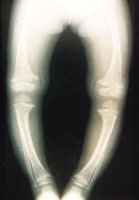

구루병에 걸리면 팔과 다리가 구부러지는데, 특히 다리가 많이 구부지는 오다리 O형 및 X형 모양이 되기도 합니다. 골절되기도 쉽지만 임상 증상을 나타내는 일은 별로 없습니다.

이것은 X-ray 사진을 찍었을 때 비로소 나타나기도 합니다. 뼈의 X-ray 사진을 보면 특이적인 이상이 나타나는데, 조기에는 석회침착 부전 때문에 골 단선이 흐려져 분명하지 않게 되며, 더 진행되면 골 단선이 술잔 모양이 되고, 연골 측이 조금 투명하게 됩니다.